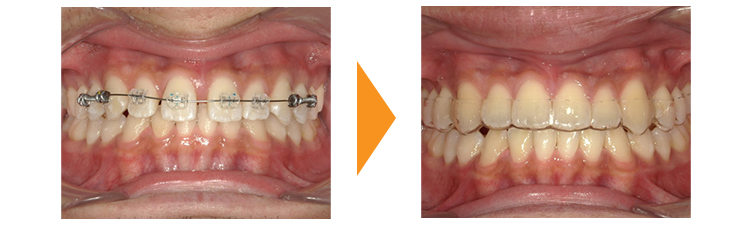

大学4年生で就職による転居の可能性もあったため、短期間で終わる部分矯正を行うこととしました。就職活動への影響も不安に思われていたためインビザラインでの部分矯正を選択されました。

下顎は動かさないですが出っ歯を改善するための支えとするためインビザラインのマウスピースは上下とも入るようになります。

顎間ゴムの使用の協力性も良く上顎前歯が中に入り、すきっぱもきれいに改善し大変喜んでいただけました。

下顎は動かしていないため、上顎を中に入れられる限度は下の前歯の位置までとなります。

すきっぱは後戻りがしやすい歯並びなので、矯正後は歯の裏側からワイヤー固定を使用し、マウスピースも継続して使用する必要があります。

ホワイトニングも行っているため歯の色もきれいになりました。

| 初診時 | 21歳8か月女性 |

|---|---|

| 主訴 | 上の歯の出っ歯とすきっぱが気になる |

| 期間 | 約8か月 |

| 矯正 | インビザライン・IPR・顎間ゴム |

| 費用 | 基本検査22,000円・契約料495,000円・調整料5,500円/月(税込) |

| 治療上のリスク | 歯磨き不良の場合はむし歯になる可能性。 習癖に伴う後戻りの可能性。 |